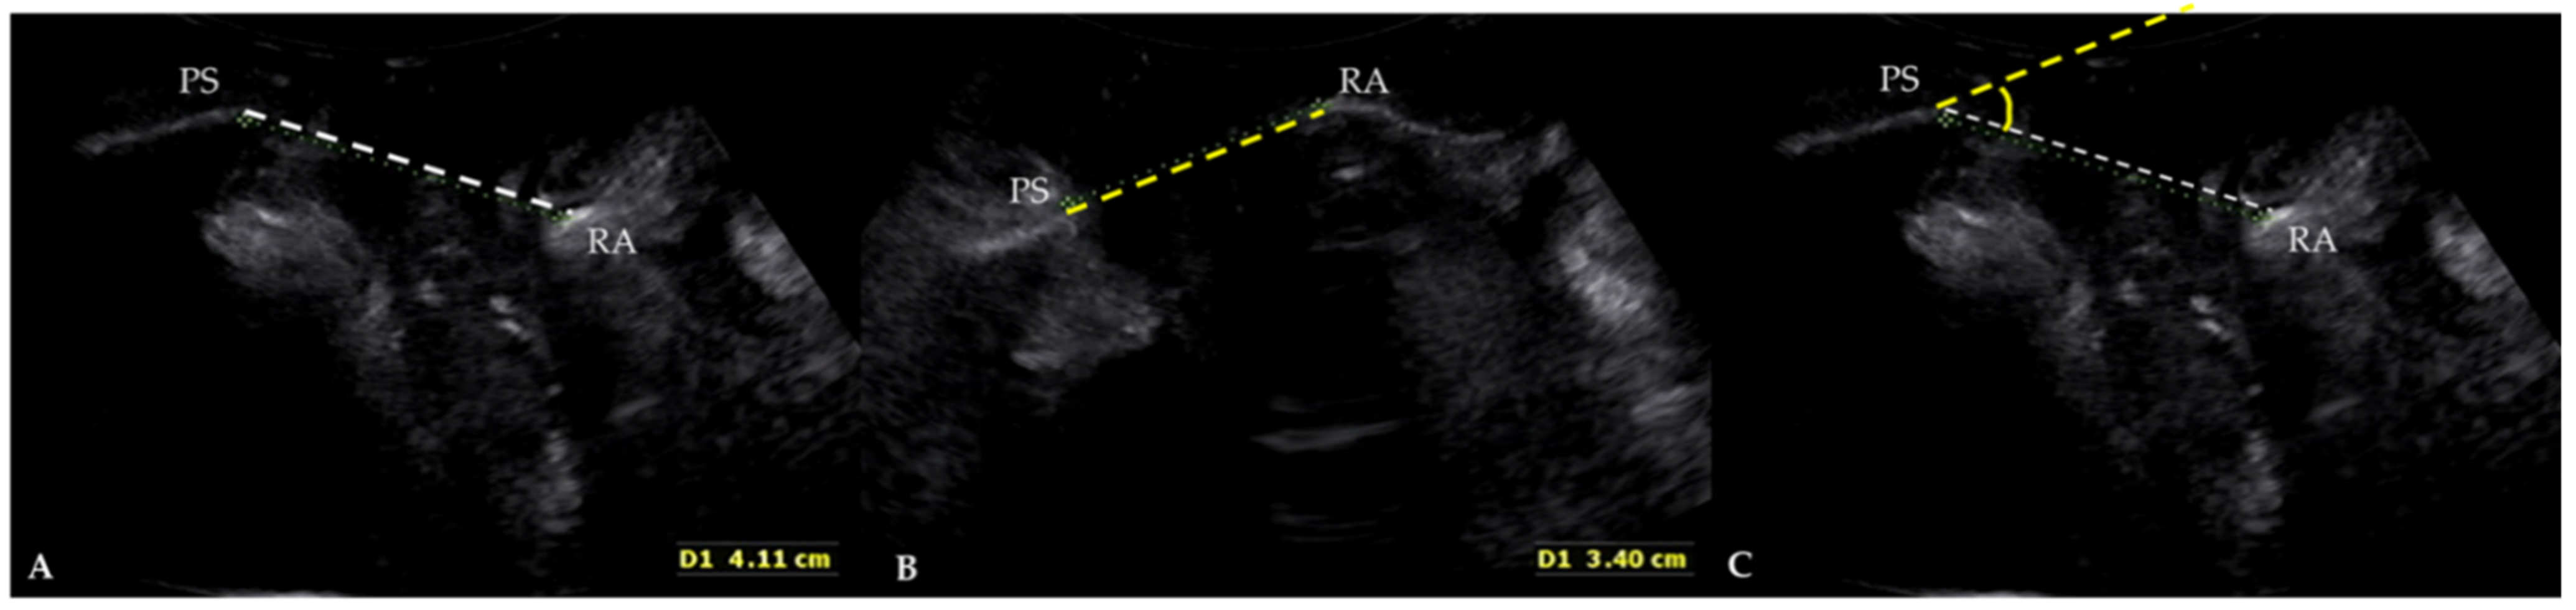

A New Angle Measurement in Translabial Ultrasound as an Adjunct for the Diagnosis of Pelvic Organ Prolapse

| Angle difference (°) † | 17.56 ± 10.70 | −18.14 to 74.79 |